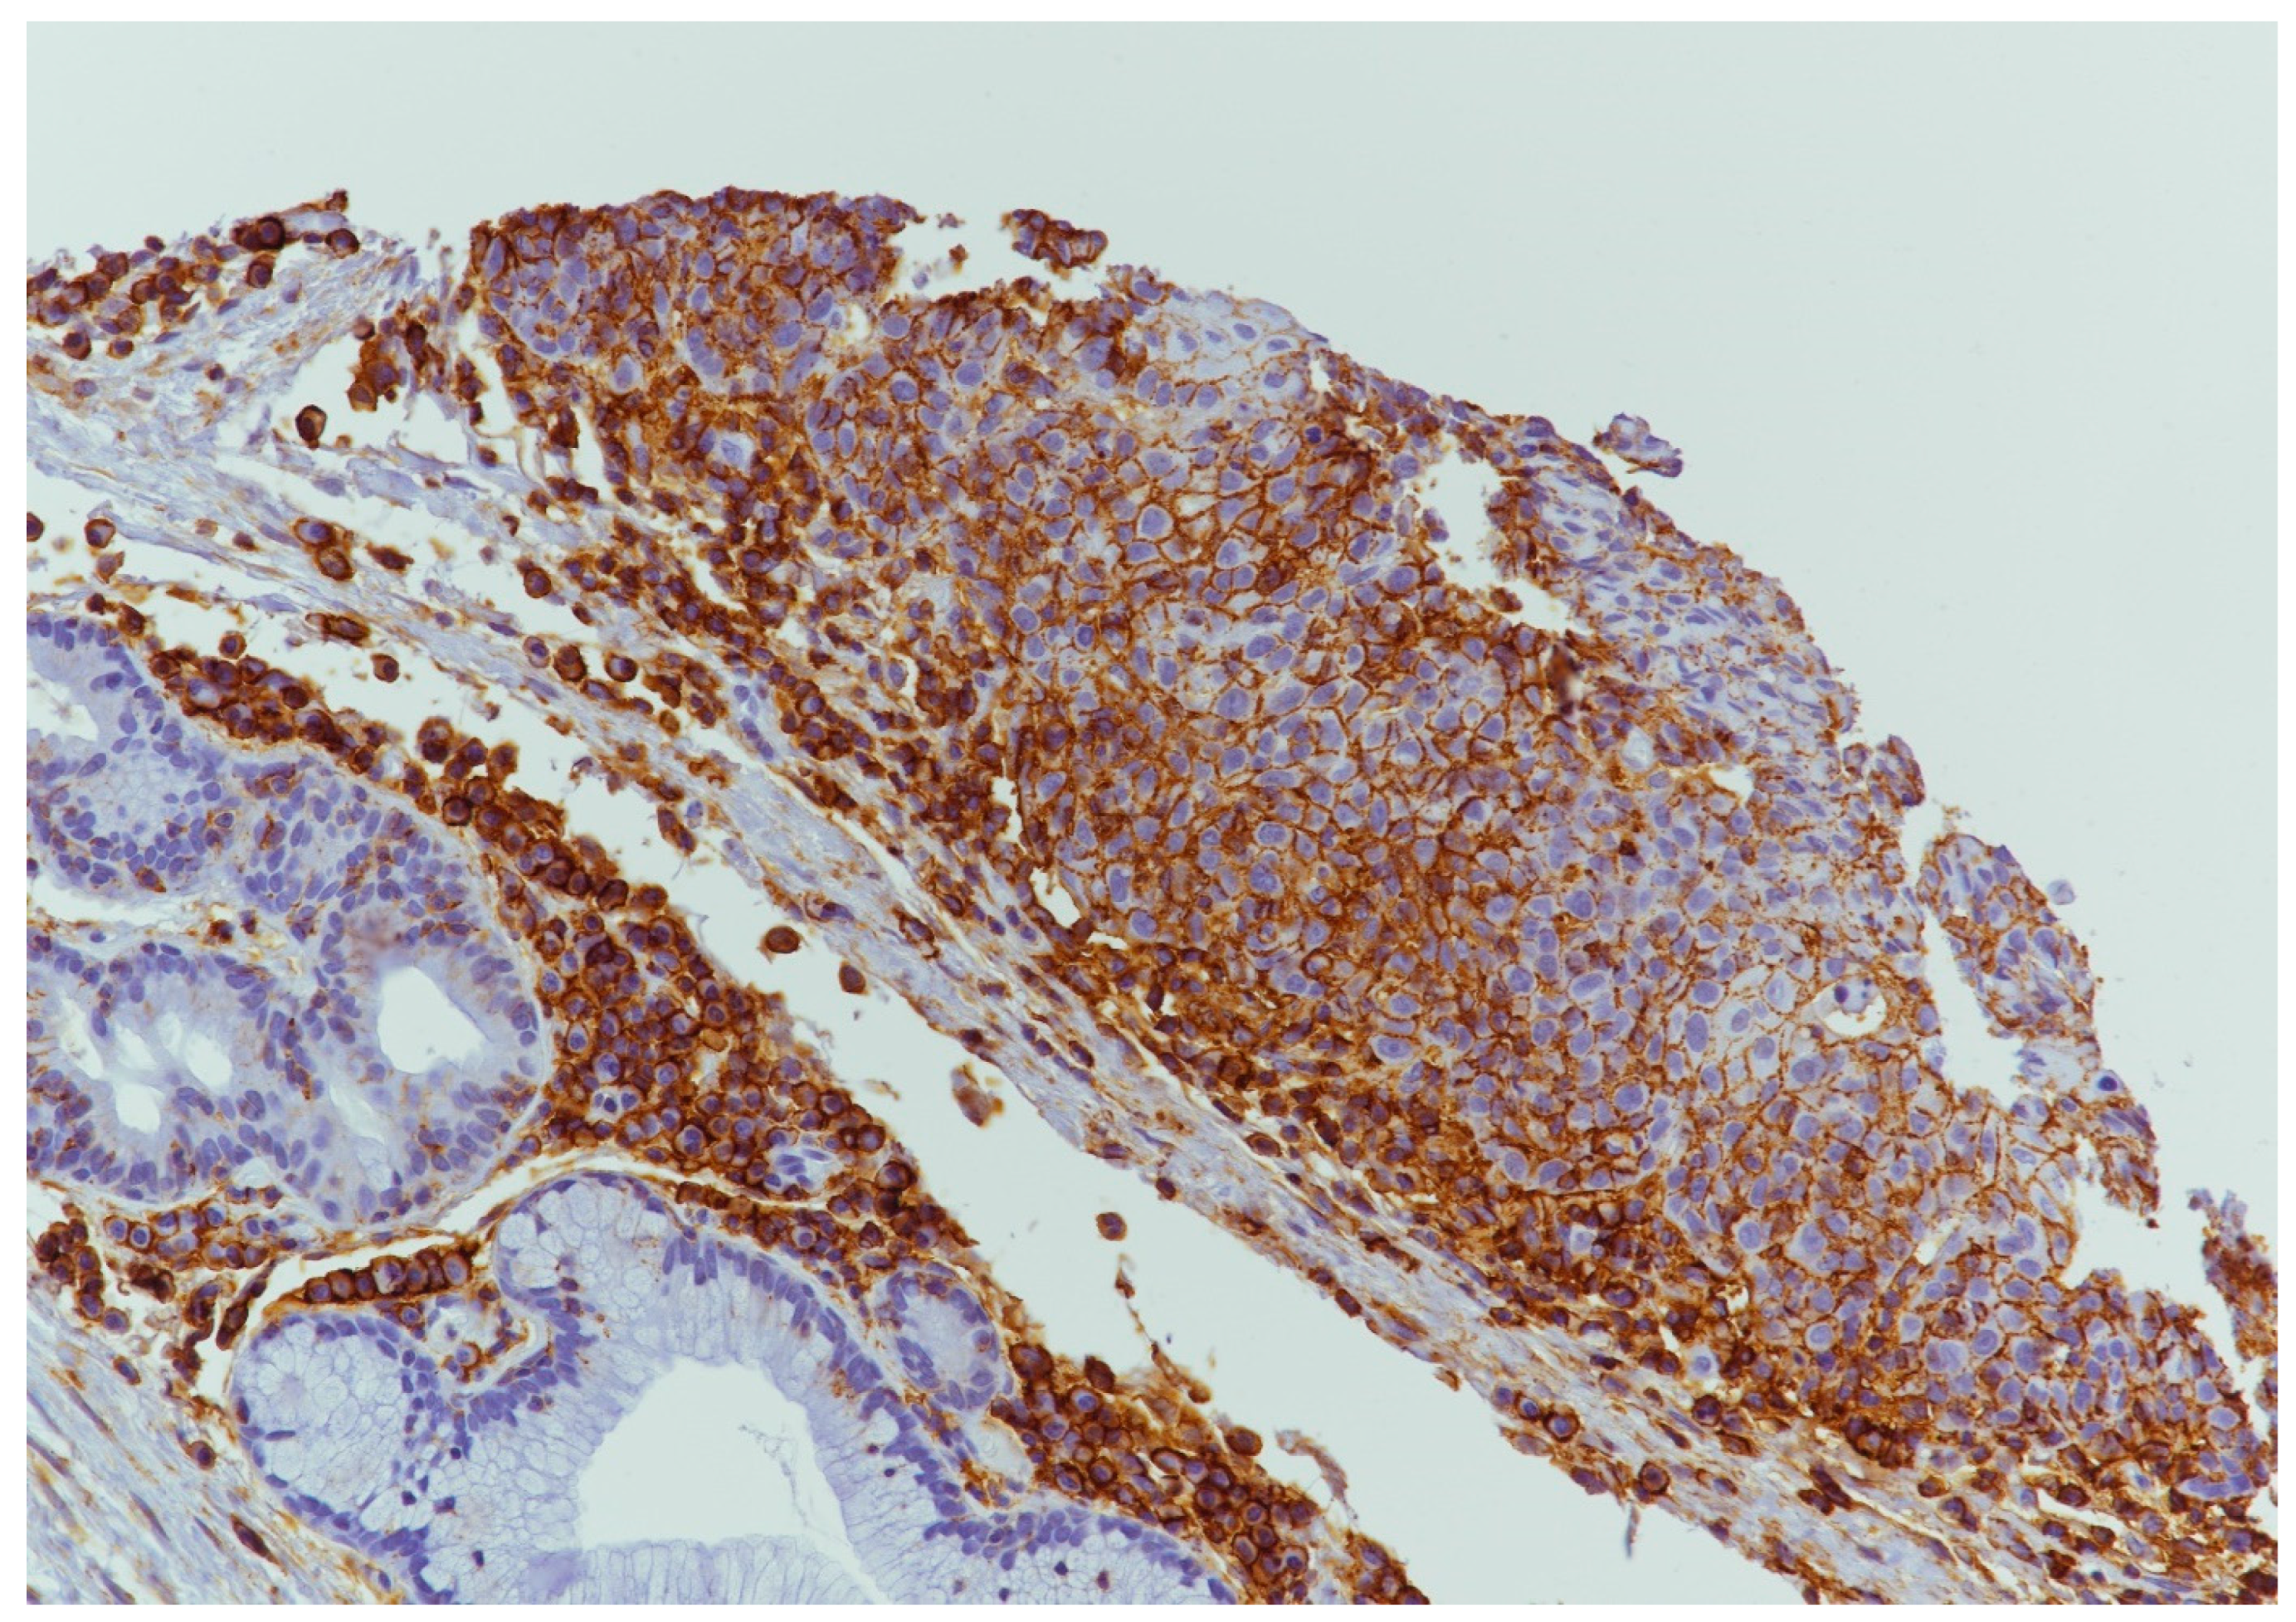

4.2. CD44 Expression

4.3. PDL1 Expression

4.4. ATG7 Expression